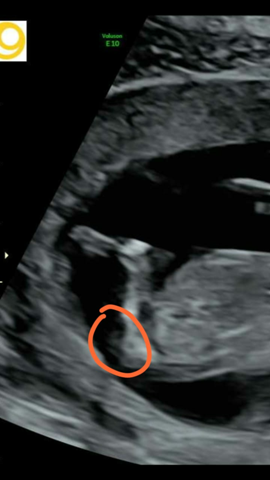

Erkennt Ihr An Dem Bild Das Geschlecht Schwanger Wer Noch

Geschlecht Auf Bild Erkennen Kann Mir Jemand Ne Antwort Geben Was Man Da Sieht Schwangerschaft Baby Frauenarzt

Nub Theorie Geschlechterbestimmung Per Ultraschall Liliput Lounge

Die Nub Theorie Fruhe Geschlechtserkennung Des Babys

Ssw 18 Geschlecht Erkennen Beim Ultraschall Rubbelbatz

Ssw 18 Geschlecht Erkennen Beim Ultraschall Rubbelbatz Ultraschall Ultraschallbild Baby Geschlecht Ultraschall